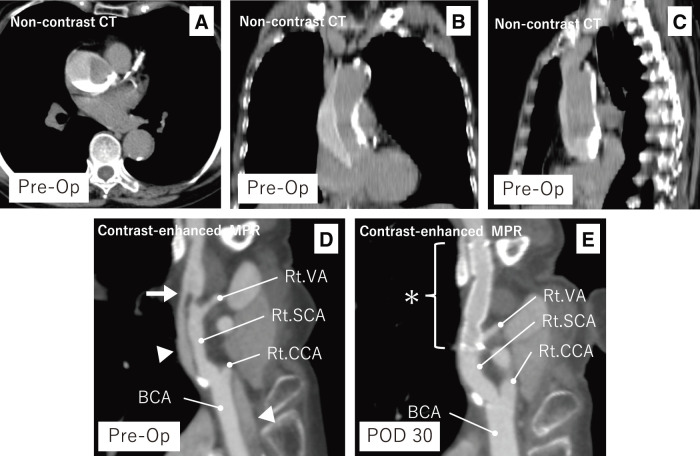

Iatrogenic type A aortic dissection (TAAD) is a rare but potentially fatal complication of coronary angiography. We report a case of iatrogenic retrograde TAAD originating from the right subclavian artery. Endovascular entry closure using a stent graft led to resolution of the false lumen and favorable aortic remodeling. The patient remained free from cardiovascular events over a 4-year follow-up. This case highlights the potential efficacy of endovascular treatment, even in retrograde TAAD with its entry located in the subclavian artery.